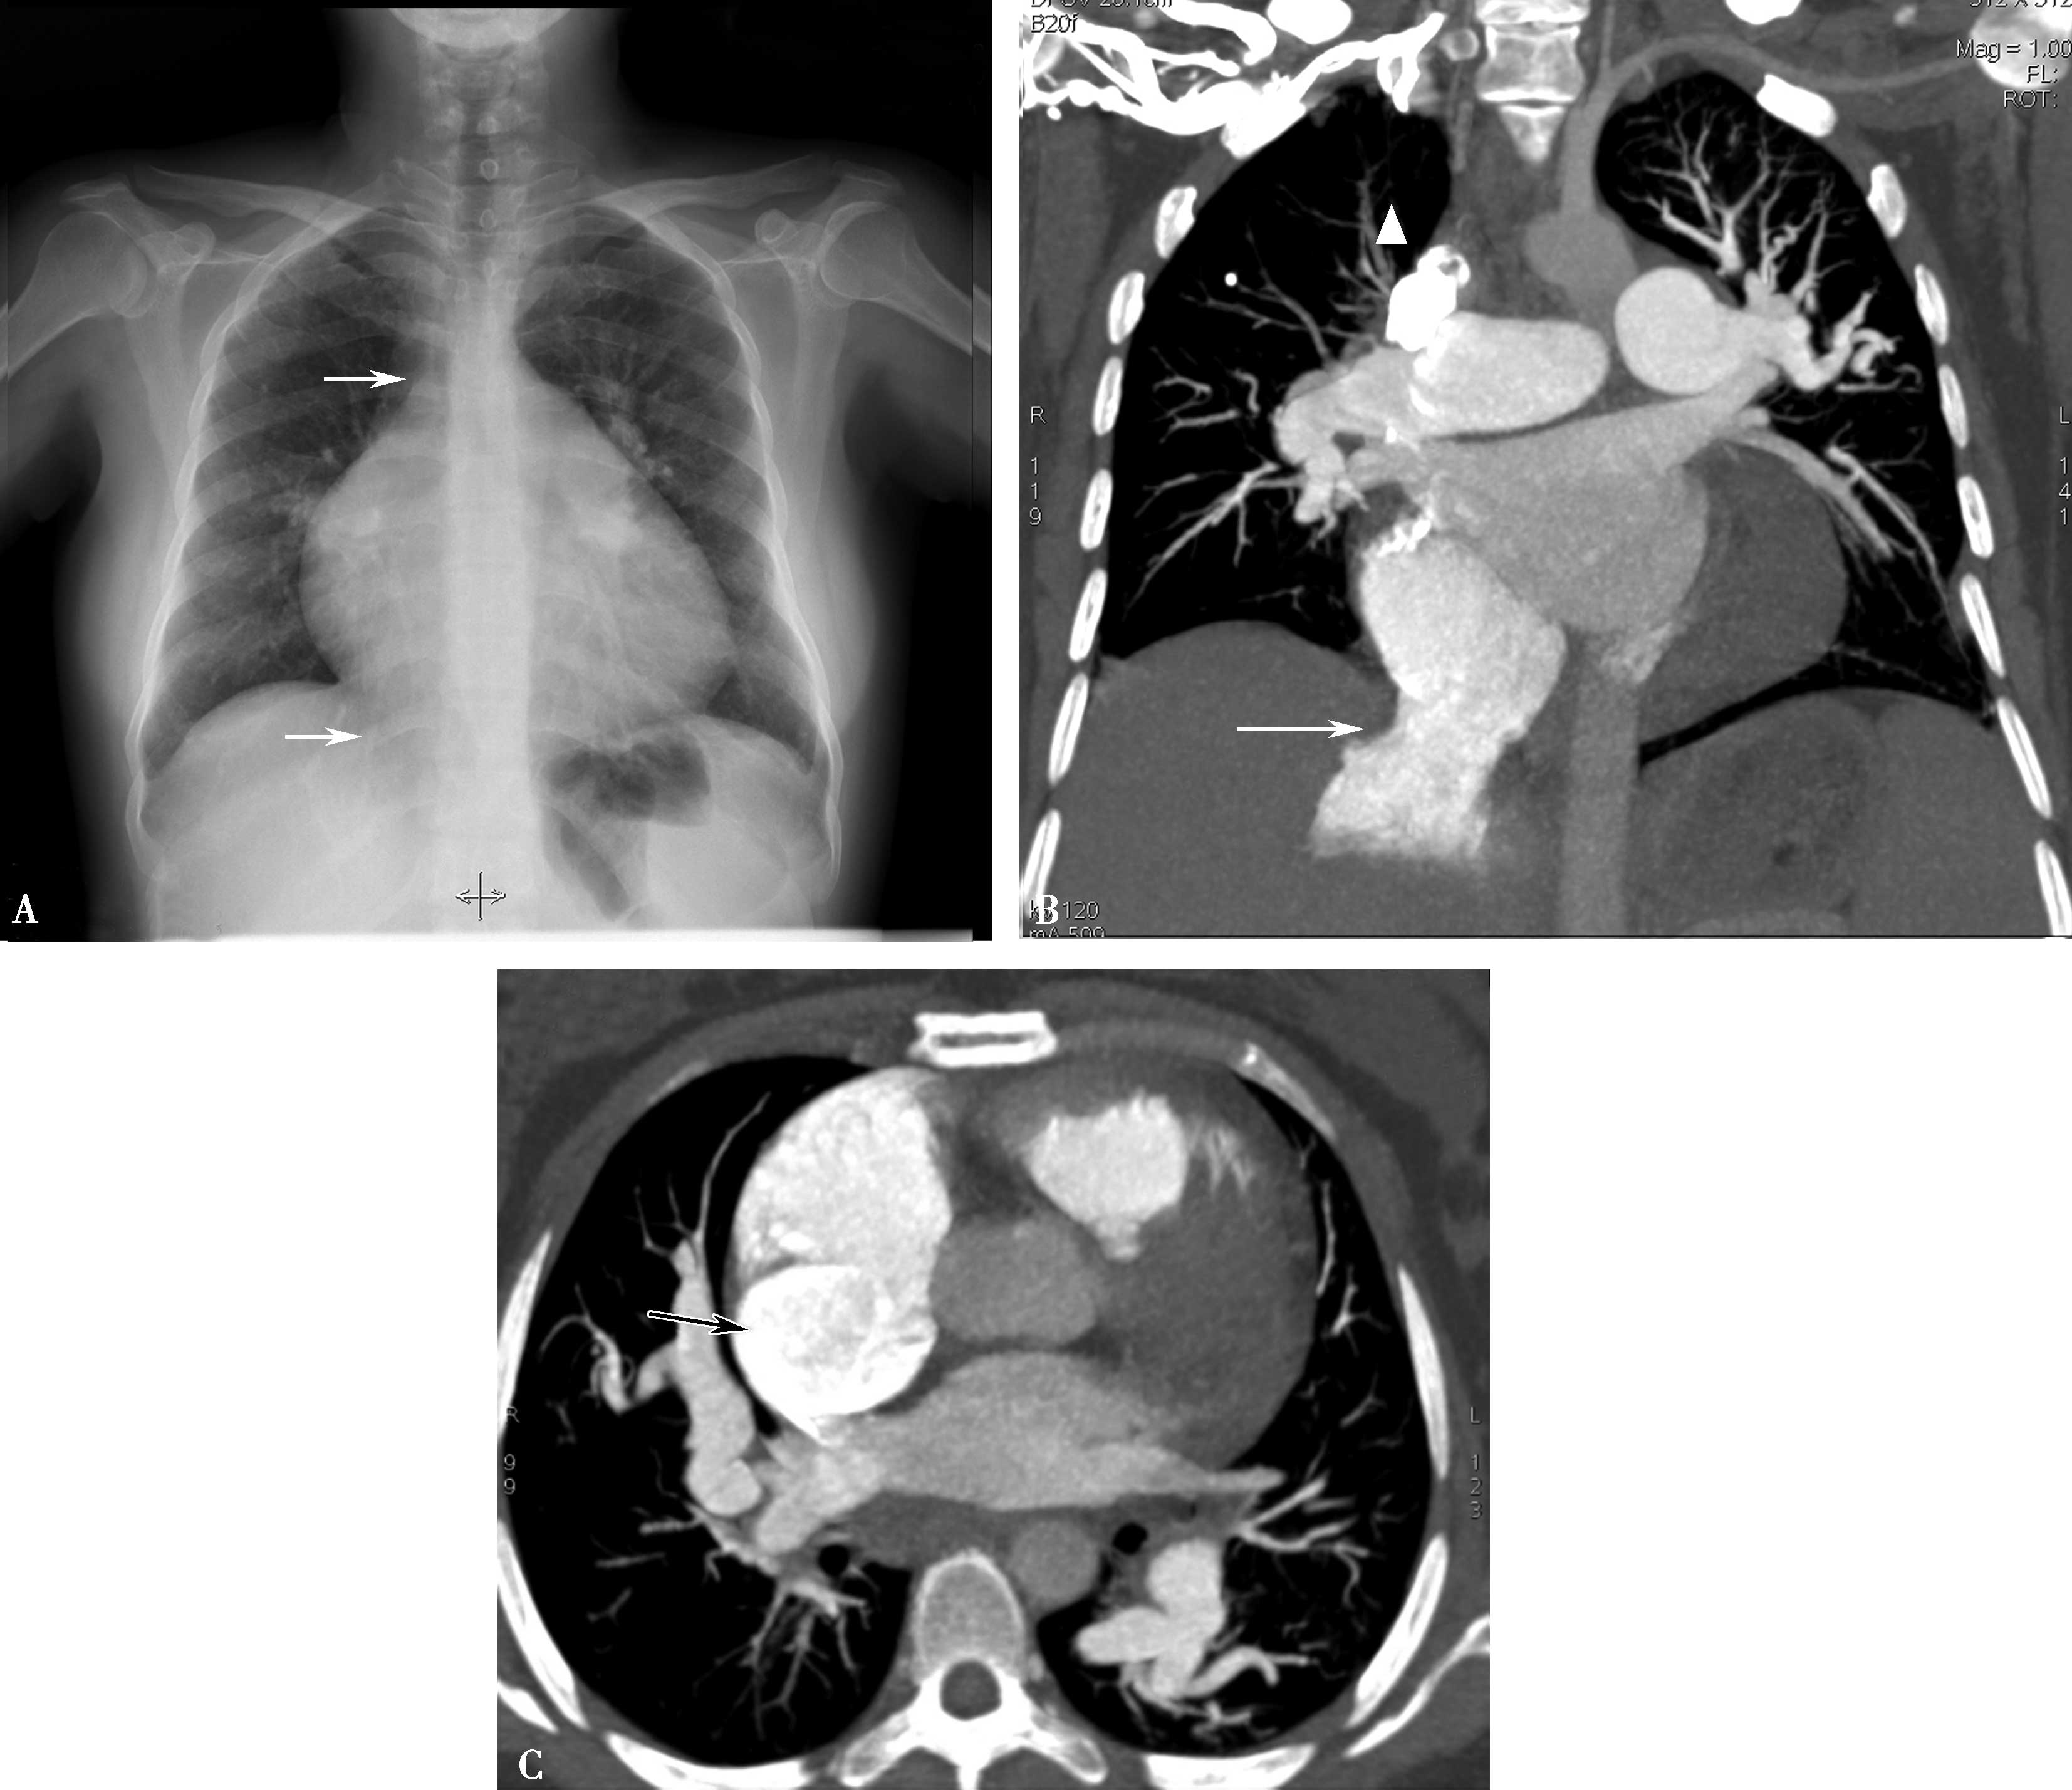

(二)双期扫描法(图8-1-5)

图8-1-5 CTPA两期扫描应用:患者,男,37岁,二尖瓣狭窄,肺循环高压,怀疑肺栓塞。第一期右肺下叶基底段对比剂充盈不充分(ABC↑);第二期充盈充分(DEF↑),排除肺栓塞诊断